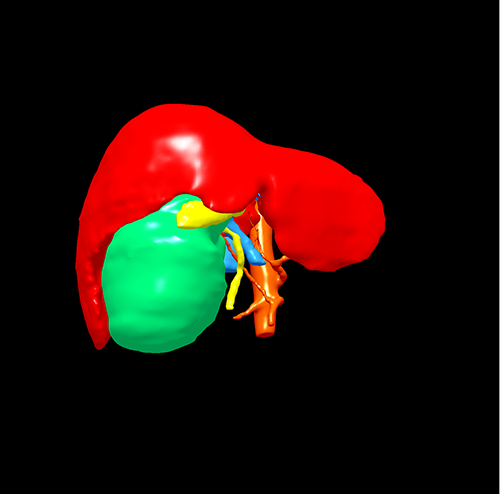

右肝胆管囊腺瘤----S5囊腺瘤切除、胆囊切除